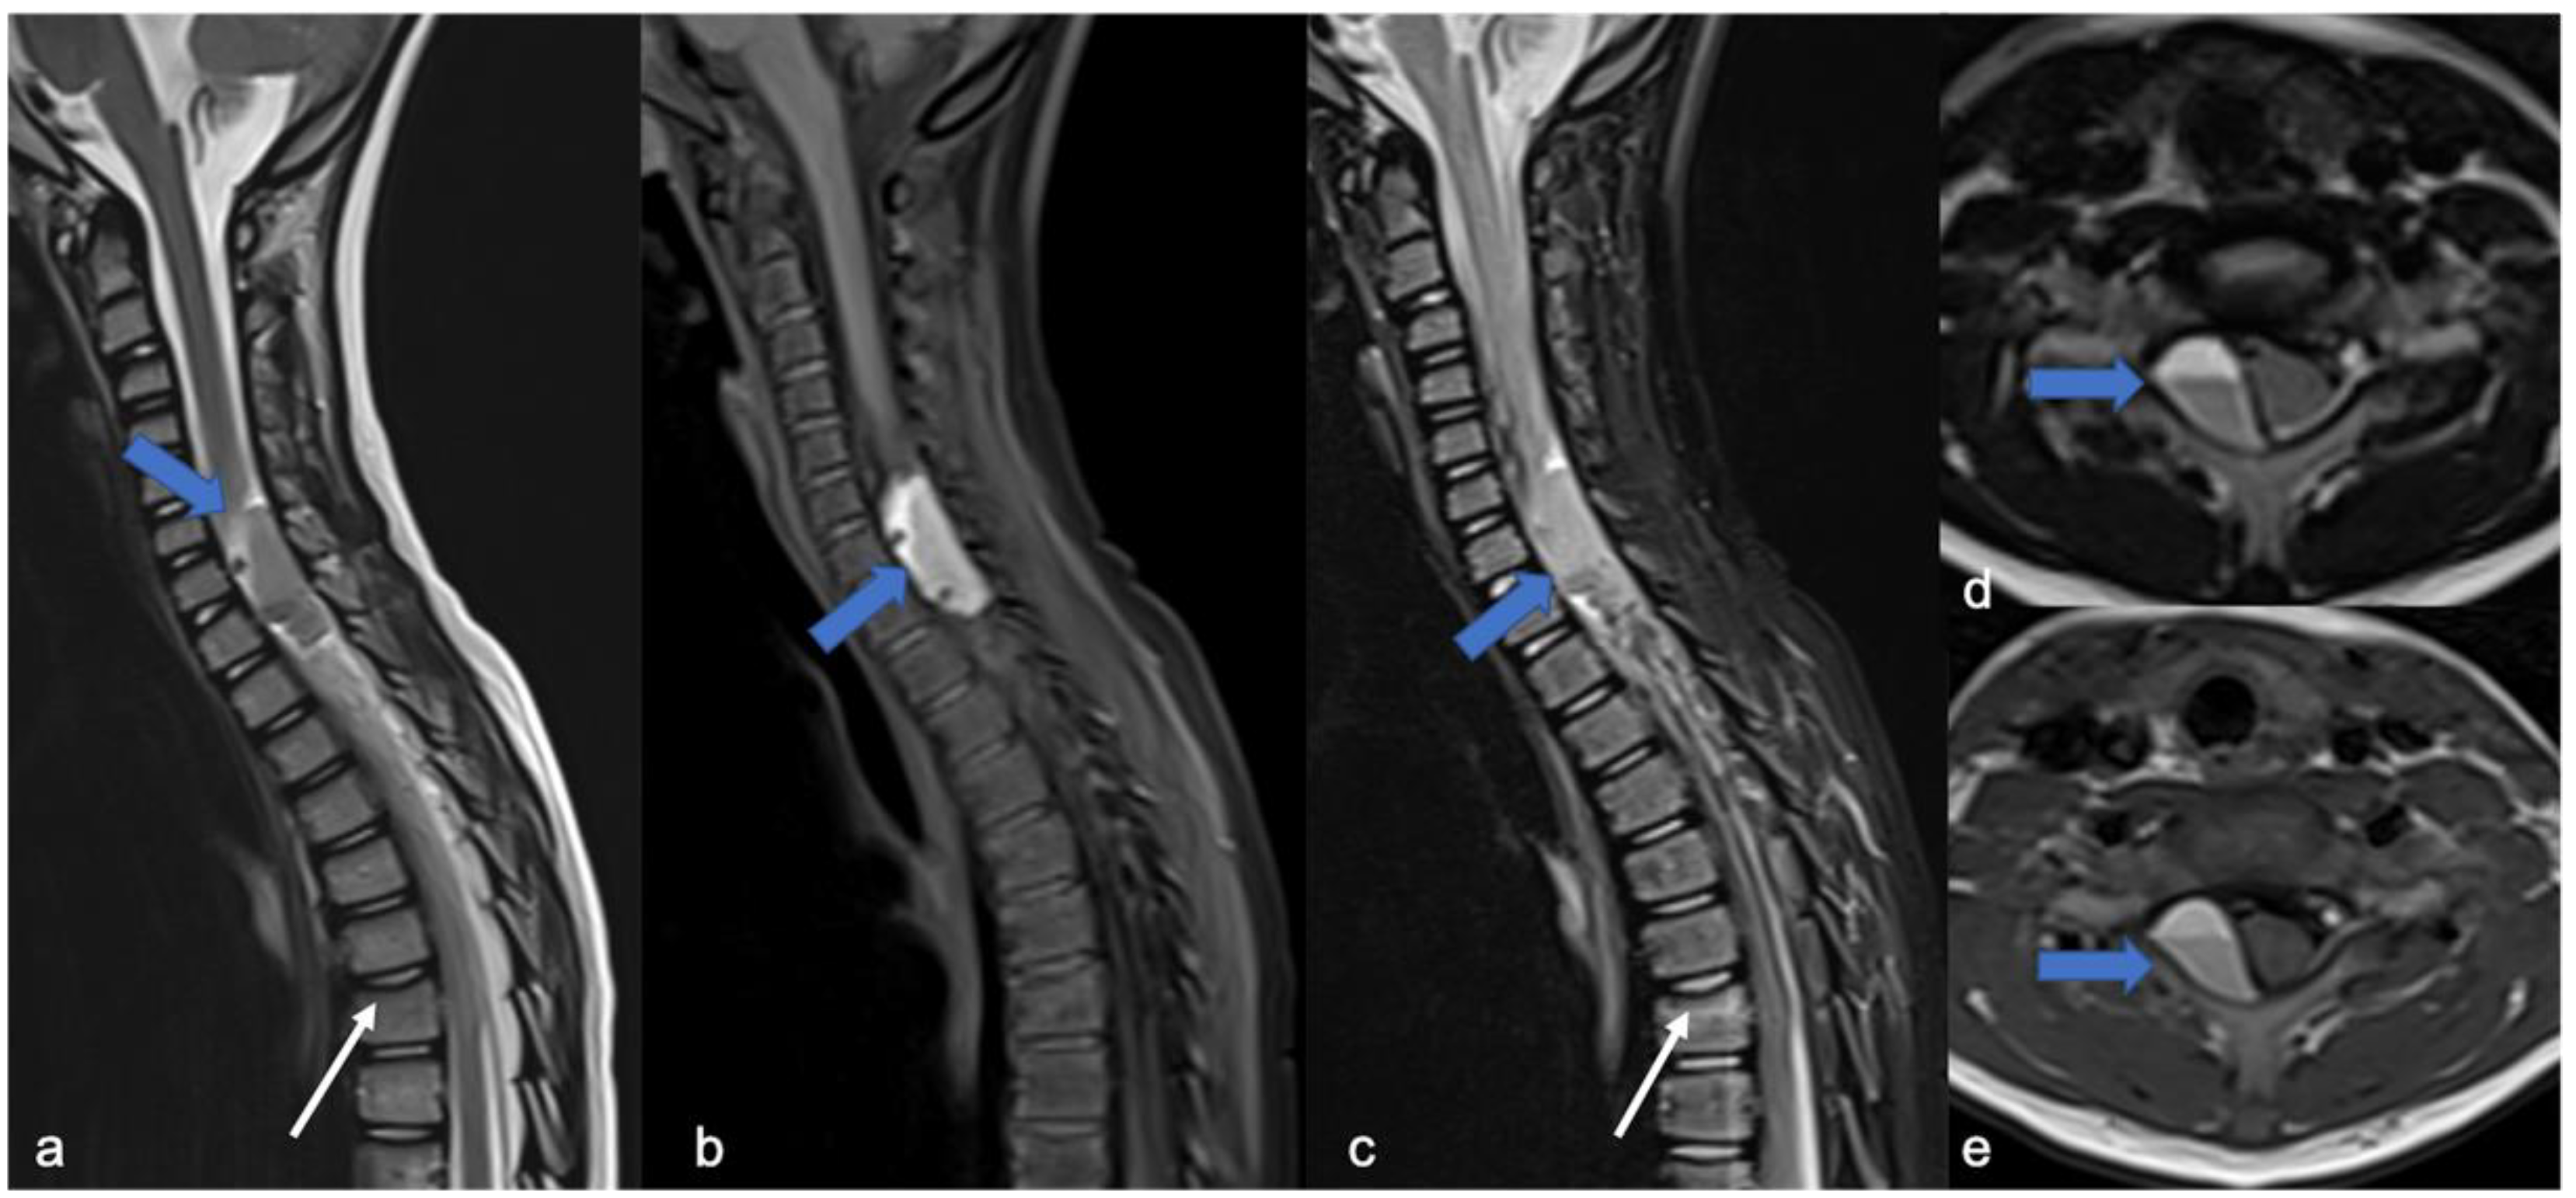

3. Ependymomas